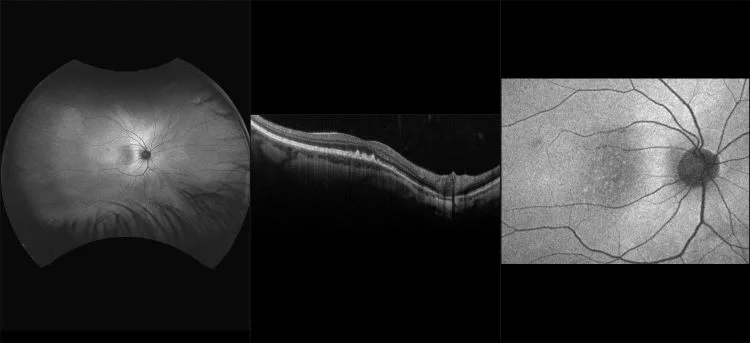

MonacoPro - Wet AMD with Macular Drusen and Sub-Retinal Fluid, RG, OCT

Age-related macular degeneration is found in two forms 1. Dry early form. 2. Wet (serous leakage or whole blood). Early dry form typically has drusen (usually around 63u) and RPE degeneration and only needs periodic follow-ups, intermediate dry form has large drusen (>125u) and RPE degeneration and proliferation which requires examinations every 3 to 6 months depending on the severity of the presentation.